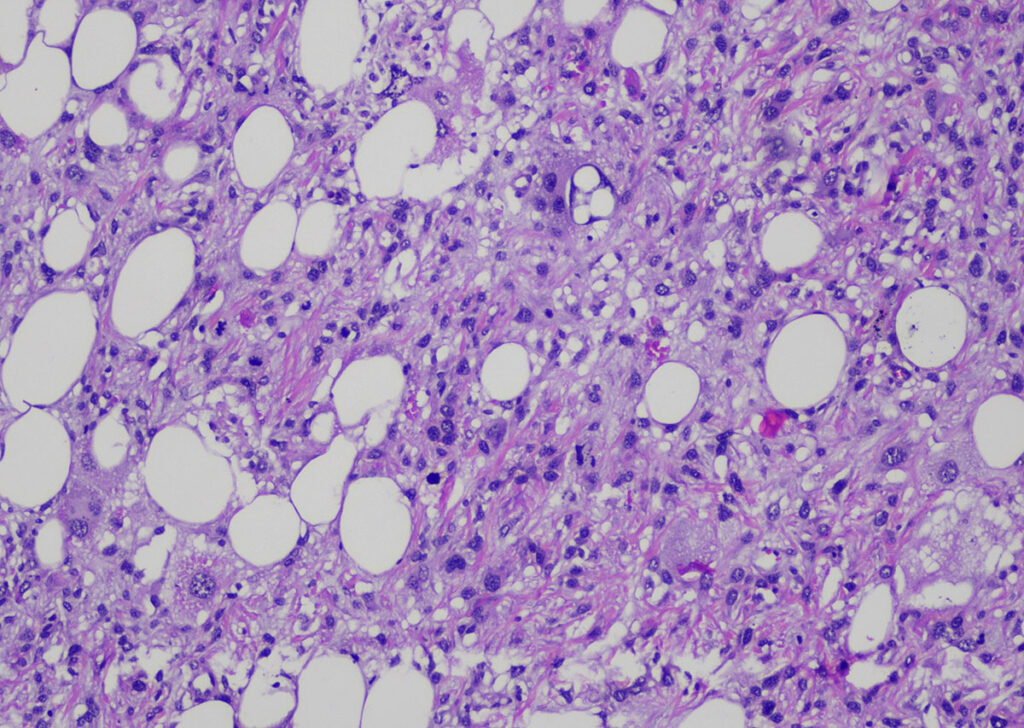

Beim Meerschweinchen dominierten die mesenchymalen Tumoren in der (Unter-)Haut. Es wurden insgesamt 508 mesenchymale Tumoren diagnostiziert, davon waren 365 gutartig und 143 Neoplasien wurden als maligne eingestuft. Die Tumoren teilten sich auf in 325 Lipome, 13 Fibrome, 13 Fibrolipome und 6 Hämangiome. Weitere 8 benigne Tumoren wurden diagnostiziert. Weiterhin wurden 80 Sarkome eingesandt (keine eindeutige Bestimmung der Ursprungszellpopulation möglich). Es wurden 29 Fibrosarkome, 24 Liposarkome (Abb. 4) und 10 sonstige maligne mesenchymale Neoplasien diagnostiziert.

Abb. 4: Liposarkom (HE-Färbung, 100fache Vergrößerung)

Bildquelle: Laboklin